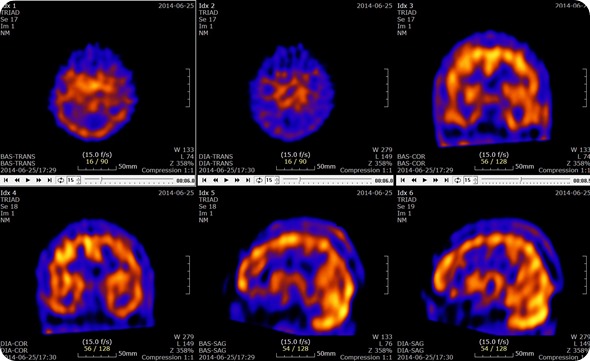

Brain SPECT with Acetazolamide Slices. Credit: U2em, shared under licenses Creative Commons Attribution-Share Alike 3.0 Unported

These rays are then detected by the gamma camera which rotates through 360 degrees around the patient. This rotation around the patient enables the cross-sectional images to be assembled three-dimensionally as in computed tomography. This means that the resulting images are able to be viewed either as a three dimensional entity or as a series of thin slices through the subject.

SPECT scans are used to determine which parts of the brain are affected by various disorders including Dementia, Epilepsy and head injuries. These are characterized by too much activity in a particular area, too little activity in particular areas or asymmetrical activity across the brain where the activity should be symmetrical. These are all determined through the comparison of the scan results to the standard normal brain scans.

The flow of blood in specific areas of the brain changes as seizures begin. The change in the blood flow can be quantified on the SPECT scan, through an investigation of the differences between a scan taken before a seizure and during a seizure. This change in blood flow can be used to identify the focus of the seizures.